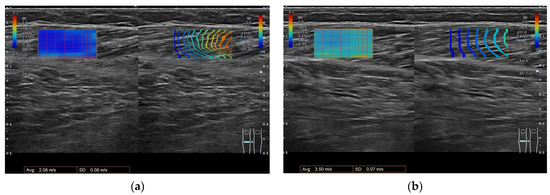

5.2. Ultrasonography